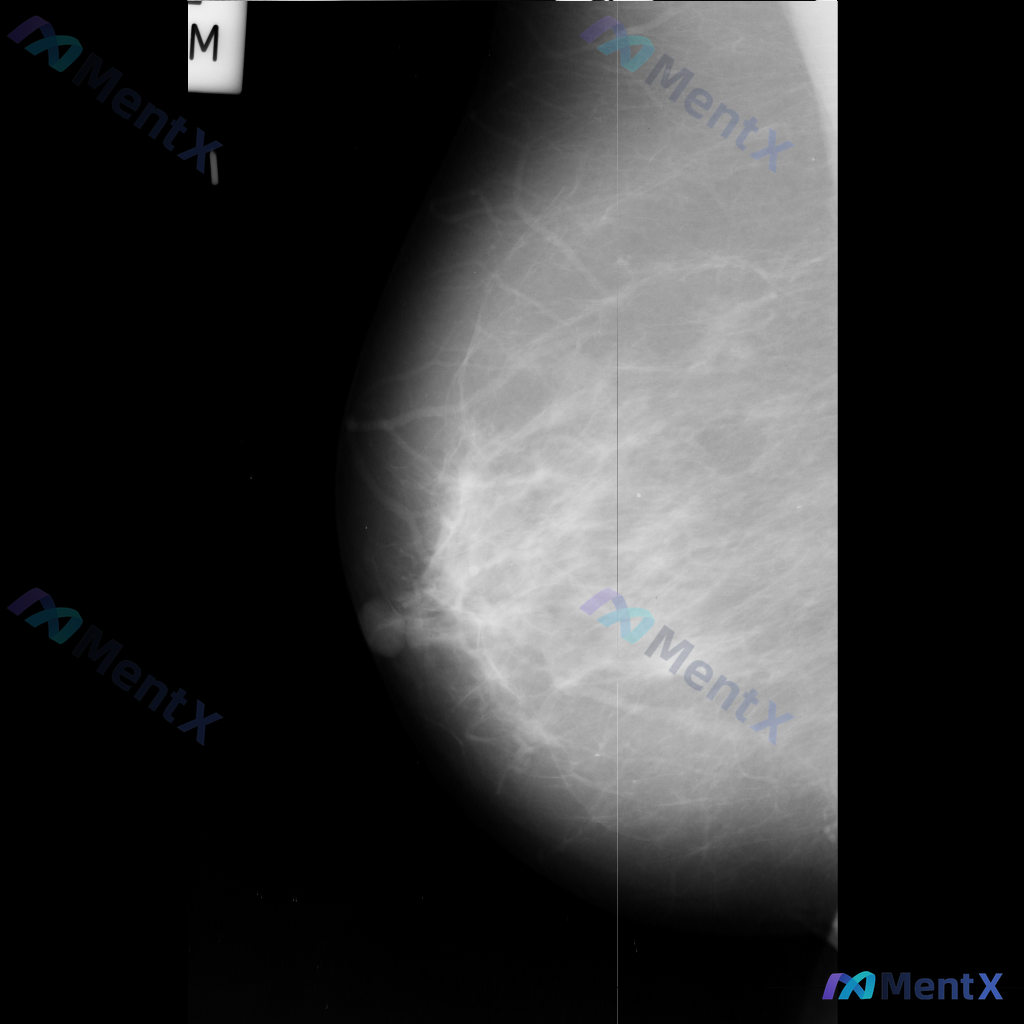

整理到一份乳腺影像的分析资料,想请大家一起讨论看看。 基本信息: - 影像类型:左侧乳腺钼靶内外斜位(MLO) 影像主要表现: 1. 左侧乳腺中上部及外侧可见局灶性结构扭曲 2. 乳腺腺体组织以纤维腺体为主,密度较高,为不均匀致密型(ACR BI-RADS C型) 3. 腺体可见多发斑片状、结节状高...